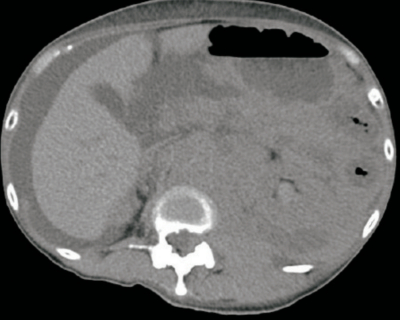

血液所見:赤血球 345万、Hb 9.2 g/dL、Ht 28%、白血球 9,000、血小板 9.5万。血液生化学所見:総蛋白 5.2 g/dL、アルブミン 2.7 g/dL、総ビリルビン 0.6 mg/dL、AST 24 U/L、ALT 13 U/L、LD 1,120 U/L (基準 120〜245) 、尿素窒素 28 mg/dL、クレアチニン1.7 mg/dL、尿酸10.2mg/dL。腹部単純CTを別に示す。